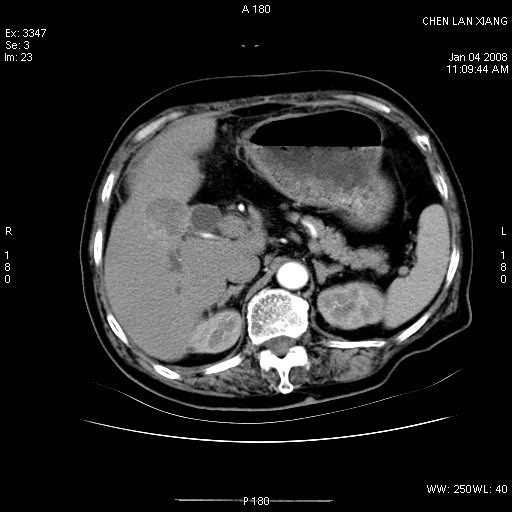

女,76岁,腹痛3-4天,b超示:肝内实性肿物,胆囊强回声,胆总管扩张.

考虑:1、胆总管下端结石伴梗阻性肝内外胆管扩张(肝左叶外侧段肝内胆管多发结石、胆管炎);

2、肿囊癌累及肝,不除外 黄色肉芽肿性胆囊炎。

1 胆总管末端结石伴肝内胆管结石,肝内外胆管扩张。2 胆囊扩大,胆囊壁不规则增厚,内见软组织密度影。考虑:慢性胆囊炎,不除外胆囊癌!

胆囊密度增高,增强后周边肝组织及胆囊窝下部周边软组织延时性不规则强化.然胆囊壁未见明显不规则增厚及肿块.左侧肝内胆管及胆总管下段结石伴胆系扩张.

考虑;胆囊炎(黄色肉芽肿性胆囊炎?),左侧肝内胆管及胆总管下段结石.

ct所见:1、 肝内胆管结石,肝内外胆管扩张。低位胆道梗阻,胆总管下端结石;2 胆囊扩大,胆囊壁不规则增厚

考虑:胆总管下端结石并肝内外胆管扩张,肝内胆管结石;

慢性胆囊炎

1)胆囊癌伴肝脏转移。2)胆总管下端结石、肝内胆管结石伴肝内外胆管扩张。